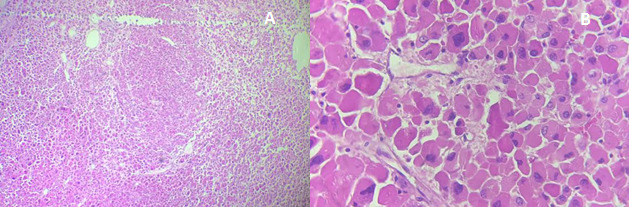

Histology revealed a well-circumscribed oncocytic adrenocortical neoplasm composed of large eosinophilic cells, without necrosis, mitoses, or venous, capsular, or sinusoidal invasion (Figure 2). The mitotic index was 0/50 HPF (≈0/10 mm²); Ki-67 labeling index was not assessed. Based on the Lin–Weiss–Bisceglia (LWB) system, the tumor met one minor criterion (size >10 cm) and no major criteria, classifying it as an adrenocortical oncocytic neoplasm of uncertain malignant potential (AONUMP), as recognized in the 2022 WHO classification .3,4 Immunohistochemistry was not performed, as morphology was unequivocally adrenocortical; in equivocal cases, a cortical panel (SF-1, inhibin-α, Melan-A, calretinin, often with synaptophysin co-expression) is recommended to confirm lineage and exclude mimics.5

The diagnosis of adrenal oncocytoma is confirmed histologically using the Lin-Weiss-Bisceglia (LWB) system.15This system classifies tumors as malignant if any major criteria are present; high mitotic rate (>5/50 HPF), atypical mitoses, or venous invasion; and as borderline with one to four minor criteria, such as necrosis, large size, or capsular/sinusoidal invasion .15Tumors lacking all criteria are considered benign. In our case, histology revealed no mitotic activity, necrosis, or vascular or capsular invasion, consistent with AONUMP.4